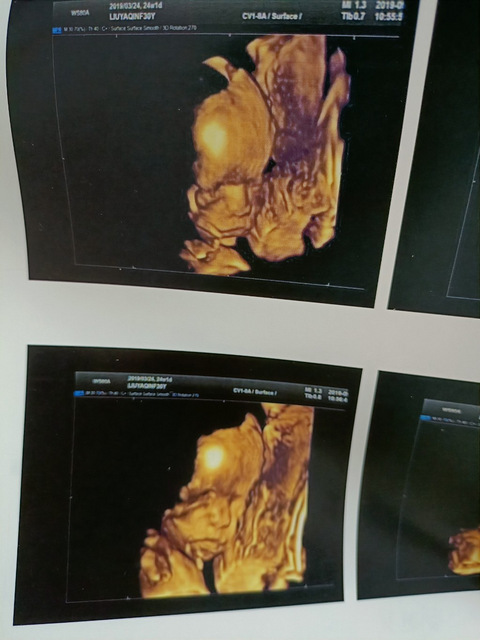

闲来无事翻了下娃的四维,你们觉得和出生后比,像嘛?

这三张都是出生后不到两个月的照片,角度没有很精准,我个人感觉完全看不出来像[ej=1F605],就当是娱乐一下吧[ej=1F61D]。而且当时四维我足足照了四次才成功[ej=1F62D],结果还给我出来这么一个不全的[ej=1F602]